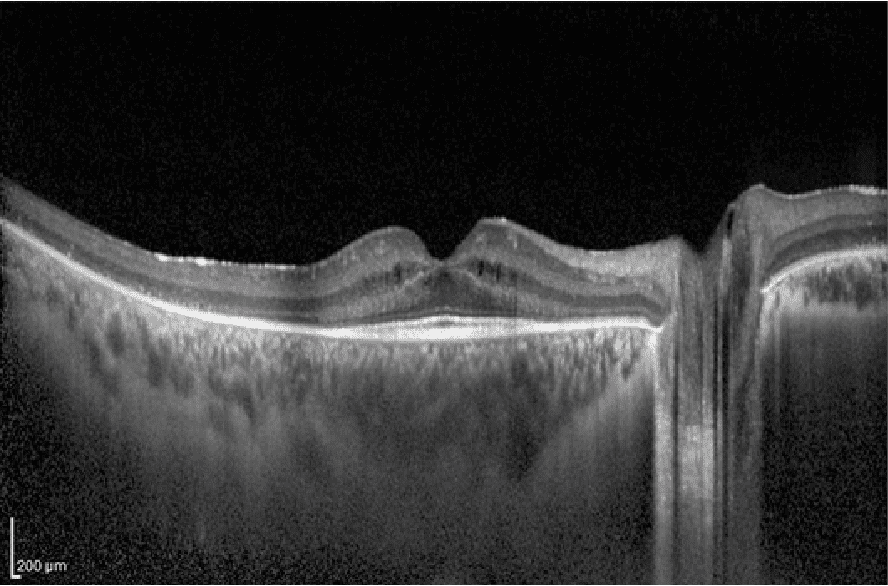

Tomografía de Coherencia Óptica (OCT)

Examen de la retina (retinografía)